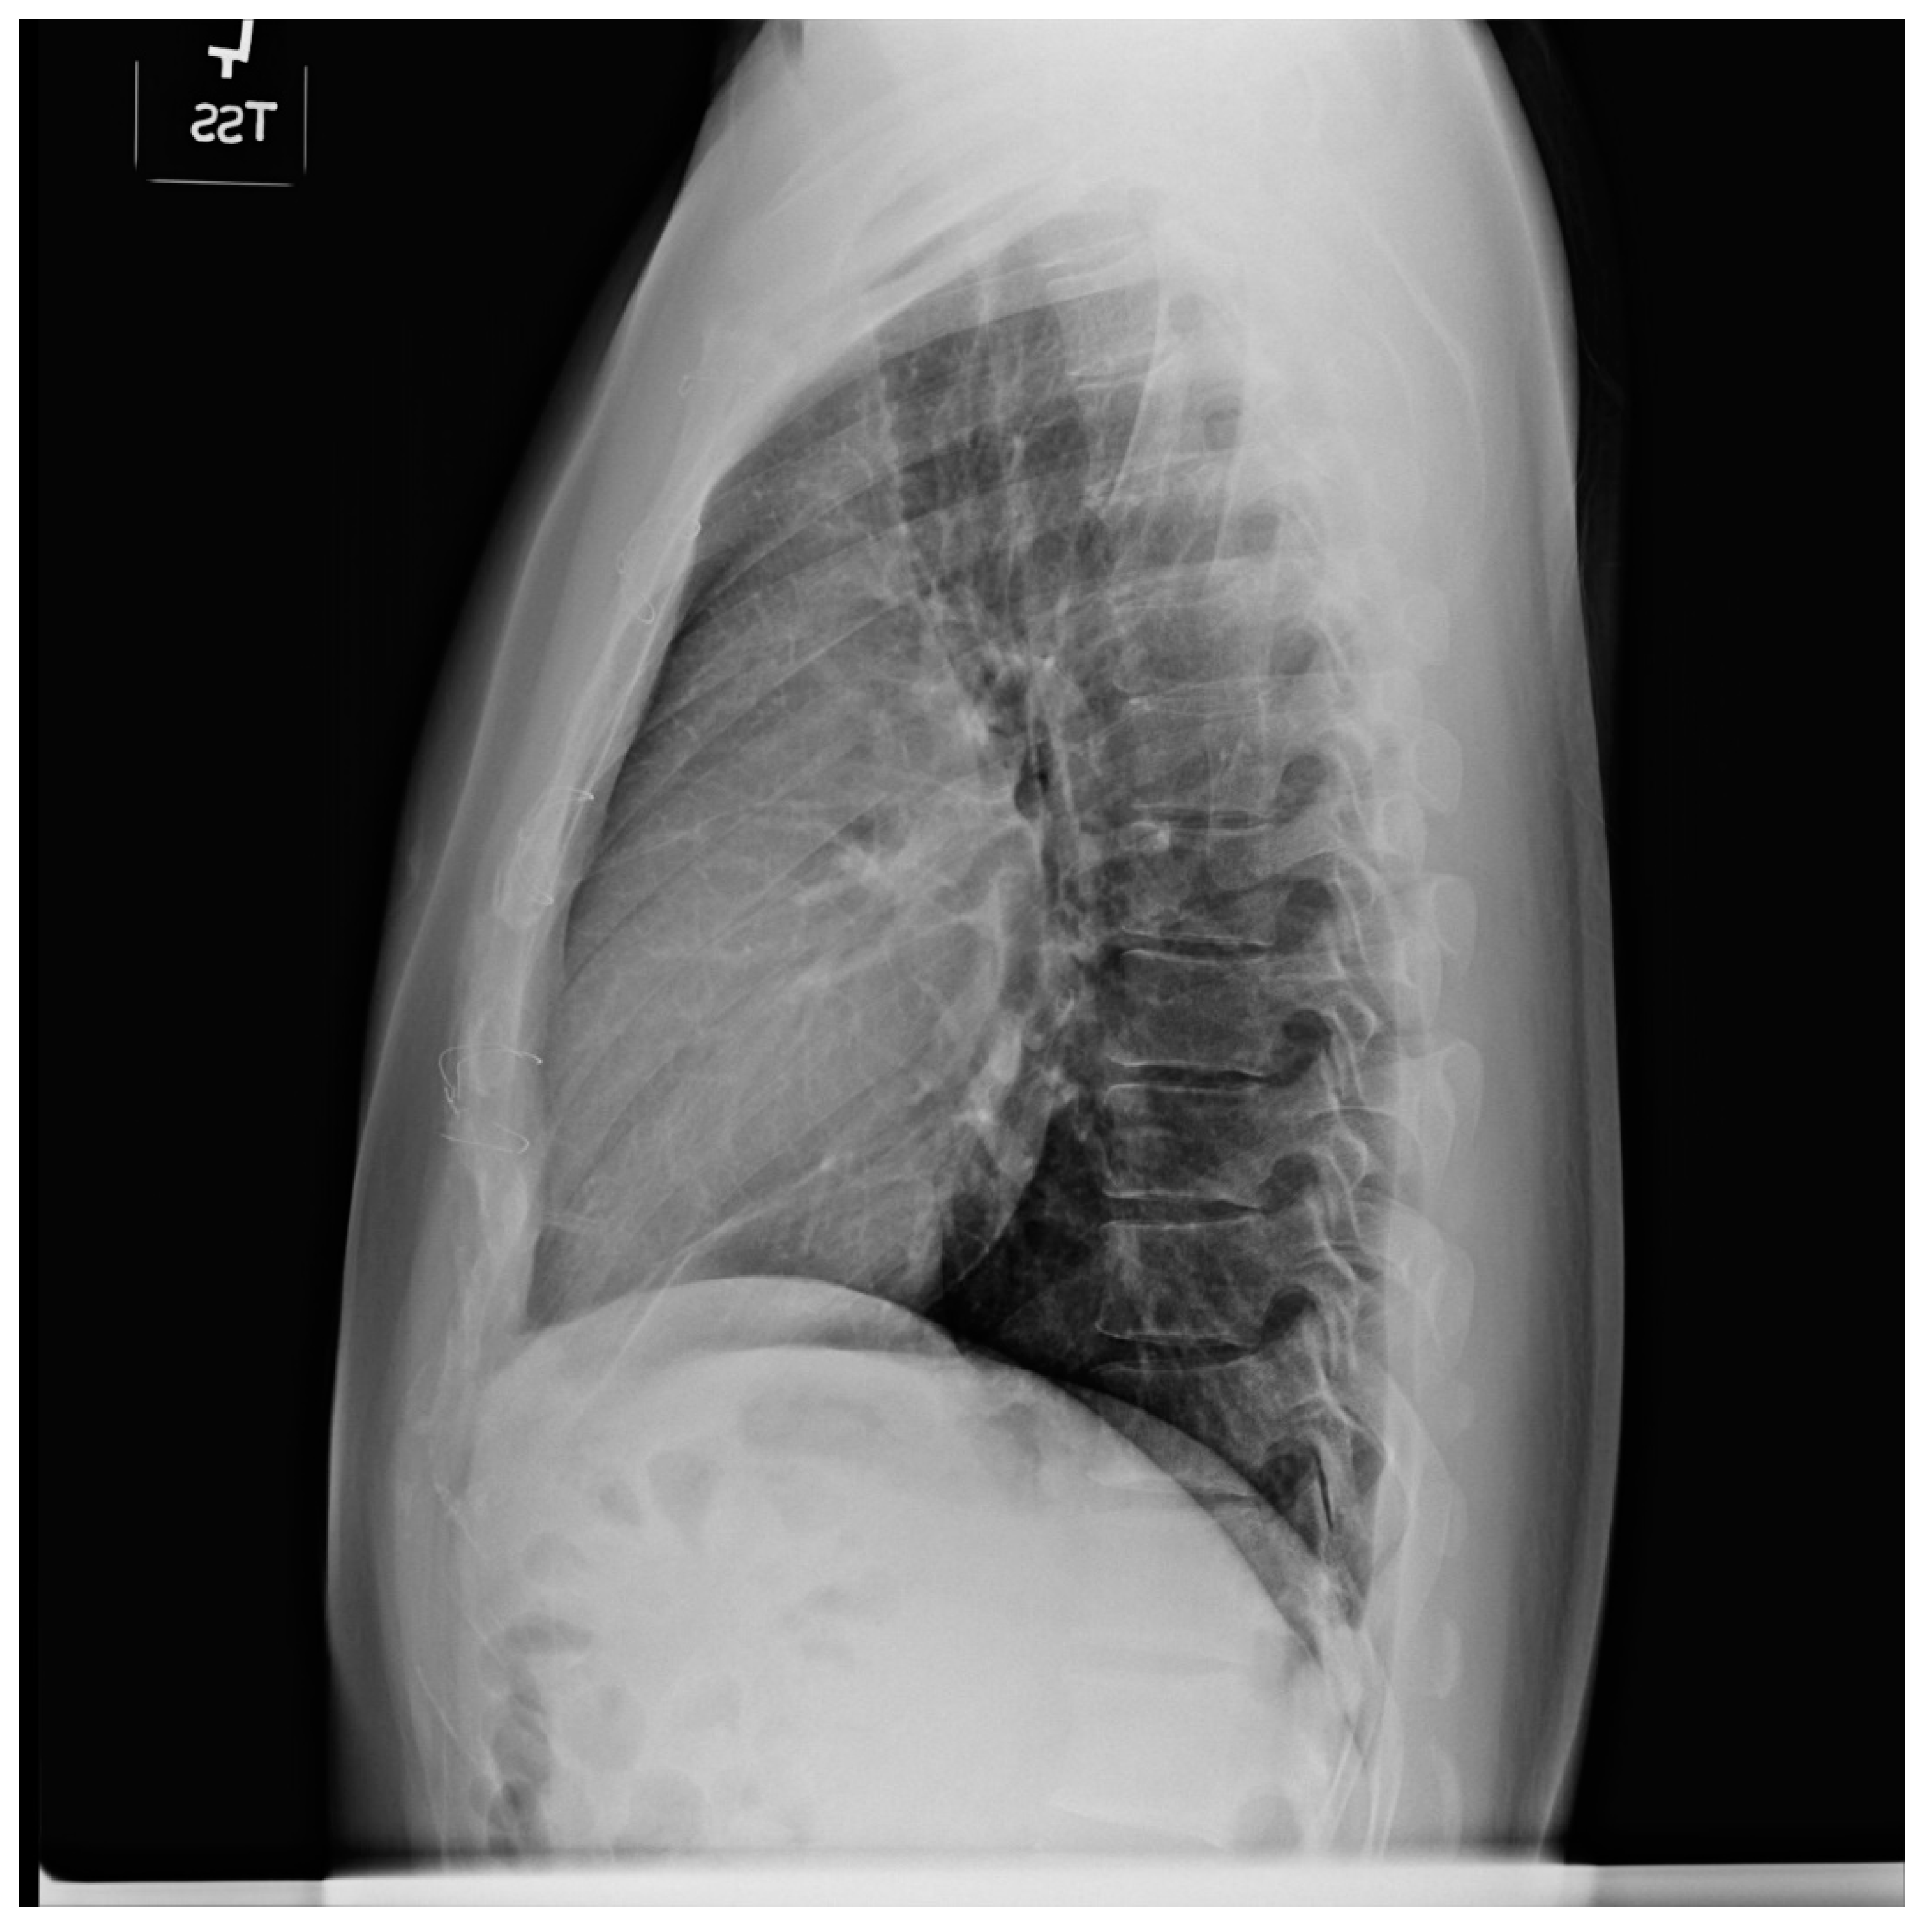

Figure 14.

Lateral chest X-ray in congenitally corrected transposition of the great arteries in adulthood: this is the lateral chest X-ray of the same 41-year-old male in Figure 13. There are sternal wires from the median sternotomy used to repair his atrial septal defect, remote from this presentation. The retrosternal airspace is opacified, suggesting right ventricular enlargement. On examination he had a holosystolic murmur of atrioventricular valve regurgitation. Doppler echocardiography demonstrated severe systemic atrioventricular valve regurgitation (the anatomic tricuspid valve), and moderate dilatation of the systemic ventricle (the anatomic right ventricle) with preserved systolic function. He underwent replacement of the systemic atrioventricular valve with a dual-tilting disc mechanical prosthesis and did well. Optimally, the transition from pediatric congenital heart disease care to adult congenital heart disease care should be a coordinated hand-off [12].